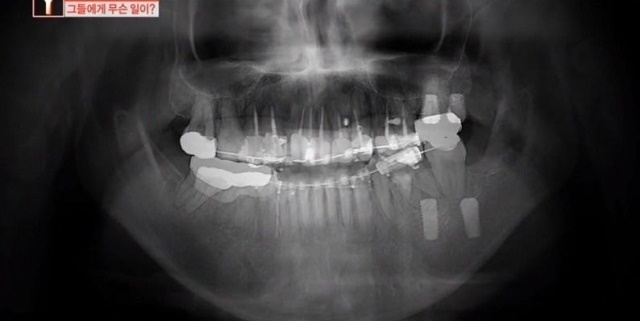

그는 치아에 생긴 얼룩만 지우고 싶었는데 치과의 원장은 윗니에 충치가 조금씩 있다며 잇몸마취 상태로 윗니 10개를 마음대로 갈아버렸다고 한다.

피해자의 치아 상태를 살펴본 다른 치과 전문의는 “충치가 확실하지 않고 충치가 없었다고 보이는데 (윗니를) 많이 갈아버린 것”이라며 “(의사가 한) 행위 자체로만 보면 상해다”라고 목소리를 높였다.

과잉진료 의혹을 받고 있는 왕지혜(가명) 원장은 “피해자분들께서는 단순히 치아 하나 치료하러 갔는데 동의도 안 받은 상태에서 8~10개 발치를 해서 피해를 많이 봤다고 얘기하더라”고 하자, 왕원장은 “치과 진료는 환자가 의식이 있는 상태에서 이뤄지는 치료다.